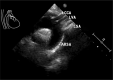

Diagnoses: Echocardiography and computed tomography angiography (CTA) confirmed arterial variations. Moreover, mild stenosis was found in the left common carotid artery (LCCA), which was considered to be the cause of dizziness.